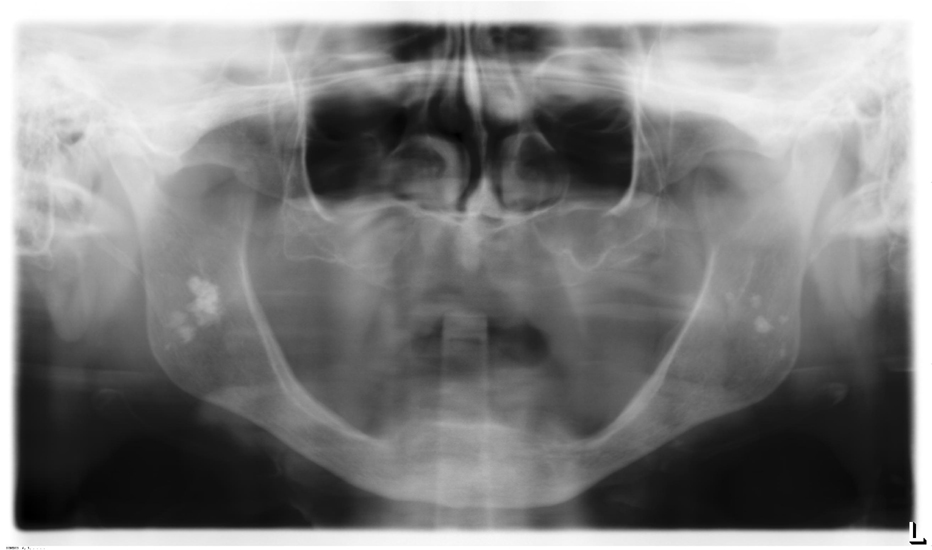

Tonsil Stones Panoramic X Ray . Since tonsilloliths can be detected on panoramic views as radiopaque lesions, and misdiagnosis. Tonsilloliths may be unilateral or bilateral. Tonsillar stones (tonsilloliths) are white or yellow concretions in tonsillar crypts that originate as a result of microorganism and cellular debris. Sometimes what is referred to as ghost images appear on a pantomograph, making a pseudotonsillolith visible on the opposite side. It might be very difficult to differentiate between. Tonsilloliths are calcifications within a tonsillar crypt, involve primarily the palatine tonsil caused by dystrophic calcification as a result of chronic. These opacities are not limited to the palatine tonsils but may also be seen in accessory lymphoid tissue. On panoramic radiographs, the palatine tonsil overlaps the mandibular ramus.